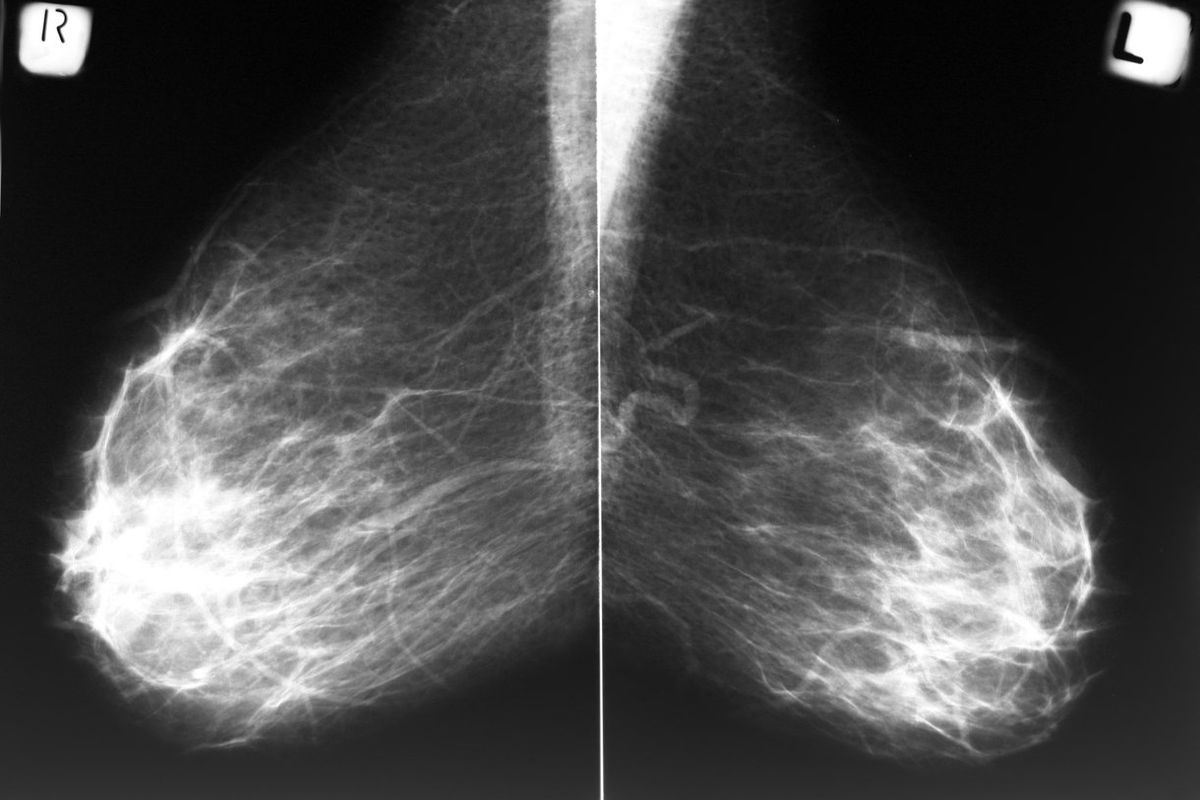

La densidad mamaria es la magnitud de tejido fibroso y glandular en tus mamas en comparación con el tejido graso. Entre más tejido fibroso y glandular tengas, más difícil será detectar cáncer en una mamografía.

Además, mamas densas dificultan la detección de cambios anormales. El tejido glandular y las masas tumorales cancerosas aparecen de color blanco en una mamografía, lo cual dificulta su distinción. A diferencia de las mamas densas, el tejido graso se muestra de color negro en una mamografía, lo cual facilita la detección de tumores.